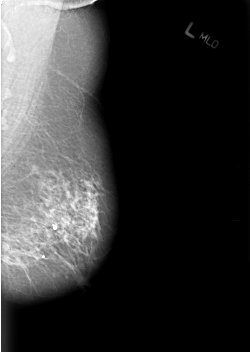

B_3025_1.LEFT_MLO

LEFT_MLO LINES 5632 PIXELS_PER_LINE 3992 BITS_PER_PIXEL 12 RESOLUTION 50 NON_OVERLAY